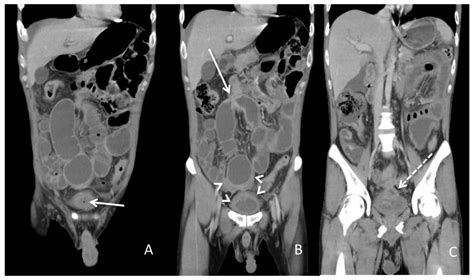

Diagnosing a colovesical fistula involves a combination of clinical evaluation, imaging studies, and sometimes endoscopic procedures. The diagnostic process typically includes:

• Imaging studies: CT scans, MRI, or barium enema can help visualize the fistula.